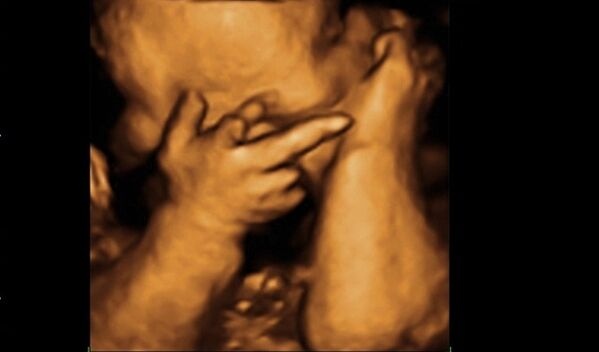

Bebekler anne karnında ne yapar?